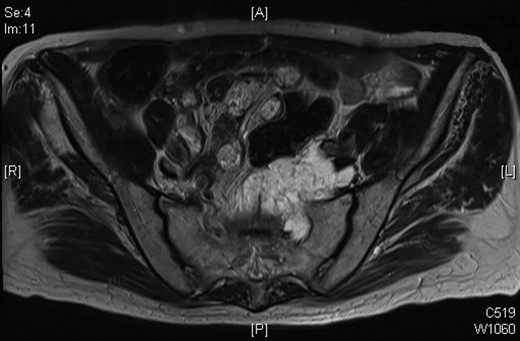

In July 2012, a follow-up MRI was done as surveillance for the mass, and this showed that the mass had extended into the left S1 neural foramen and another similar high signal area was seen to the left of the lower rectum and his CEA has continued to rise. After much discussion and in view of age and co-morbidity, together with the involvement of the pelvic sidewall, an R0 resection was not possible.

Progression of the mucinous mass on MRI in 2012. On repeated PET scanning, the mass shows minimal cellular activity.